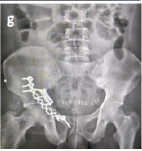

Stage one: After maintaining all aseptic precautions, we employed a lateral approach. The greater trochanter was identified with prosthesis. Greater trochanter was severely osteoporotic. There was a chance of fracture while removal of the implant. Dislocation of head of prosthesis and removal of it were done successfully (Fig. 2). Acetabular surface was deficit near 30%. Removal of surrounding tissues was done carefully. After that, we kept an antibiotic-mixed cement as a spacer (Fig. 3) and gave vancomycin powder within the acetabular cavity. After closure, we planned to perform the 2nd stage of surgery 4 weeks later. Stage two: Due to the unavailability of the implant, we had done 2nd stage of surgery 10 weeks (2.5 months) later. We used the same lateral approach with extension up to mid-thigh and removed the cement spacer. We reamed the acetabulum very carefully and found the bone very soft and fragile. For this reason, a non-cemented cup was inserted (Fig. 4) and fixed with three screws. Shaft of the femur was exposed properly and found absence/deficient of the lateral cortex of it. Prosthetic end of medullary cavity was found blocked by bone. Initially, we tried to reaming the medullary cavity under fluoroscopy guided by 7 mm reamer. It was very difficult to achieve the reaming portion at the blocked area. Introduction of stem was difficult due to the chance of re-fracture and there was a big gap, measuring 8 cm × 1.25 cm at the lateral cortex of the femur. To cover this gap, the mid-third of the fibula (harvested by fibulectomy) (Fig. 5) was used as a bone graft, which was then grafted and fixed using surgical wiring (Fig. 6). Afterward, we faced difficulty during cementing technique. During introduction of cement into the femoral medullary cavity, cement was found leaked from the space of the grafted bone. Then leakage was carefully protected. Femoral stem was introduced carefully so that it was be in a position to medullary cavity (Fig. 7). A drain tube was kept in situ, then with aseptic precautions, we closed the surface.

Following the first stage of surgery, the patient was given a combination of piperacillin and tazobactam intravenously, initially at a dose of 4.5 g/vial and then 2.25 g/vial 3 times daily for 14 days. In addition, ciprofloxacin was given orally at a dose of 500 mg twice daily for 1.5 months. She was released on the 7th post-operative day. Following the second stage of surgery, the patient was given intravenous piperacillin and tazobactam, initially at a dose of 4.5 g/vial and then 2.25 g/vial 3 times daily for 7 days. Amikacin was also given intravenously at a dose of 500 mg/mL 3 times daily for 3 days, followed by oral ciprofloxacin at a dose of 500 mg twice daily for 1.5 months. Drainage through the drain tube continued up to the 5th post-operative day. The patient remained hospitalized for 30 days following reTHA to ensure proper physiotherapy, prevent refracture due to osteoporosis, and reduce the risk of reinfection. During the recovery period, the patient received oral analgesic treatment and physiotherapy, leading to a progressive improvement in mobility. Initially relying on a walker for non-weight-bearing ambulation, the patient progressed to using canes and eventually achieved independent walking without assistance. At the 18-month follow-up, the HHS was 80, suggesting good hip status and significant improvement. She gradually resumed her normal daily activities. Post-operative X-rays of the pelvis including both A/P view and lateral view revealed that the mechanical axis was maintained and there was no loosening of the implant (Fig. 8 & 9).